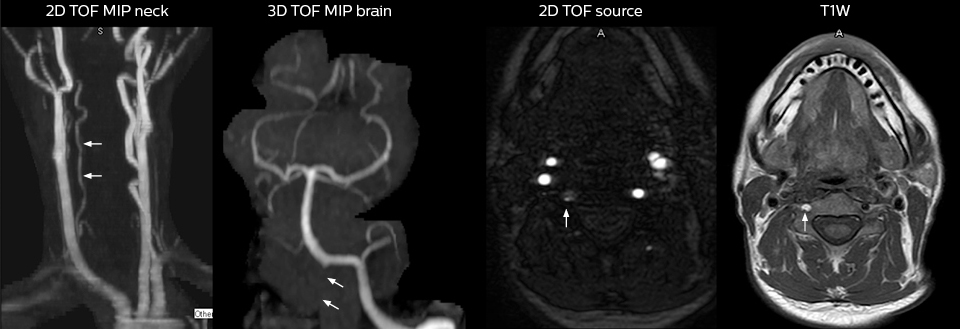

Including mDIXON TSE for robust fat suppression

“We use mDIXON TSE extensively in our spine imaging in the emergency room,” says Dr. Karis. “It’s particularly nice in that it is very robust with regard to susceptibility type of problems that would come up with traditional spectral fat-saturated images; these problems are essentially eliminated with the mDIXON technique. In our ED environment it’s really nice to have the fat-free imaging that goes along with the mDIXON technique.

“For the thoracic and cervical spine routine non-contrast exam, for example, we perform one mDIXON T2 TSE sequence, which provides us with two outputs: the fat-and-water-together T2-weighted images, as well as the water-only sagittal T2-weighted images. And then we also perform an axial gradient echo exam.”